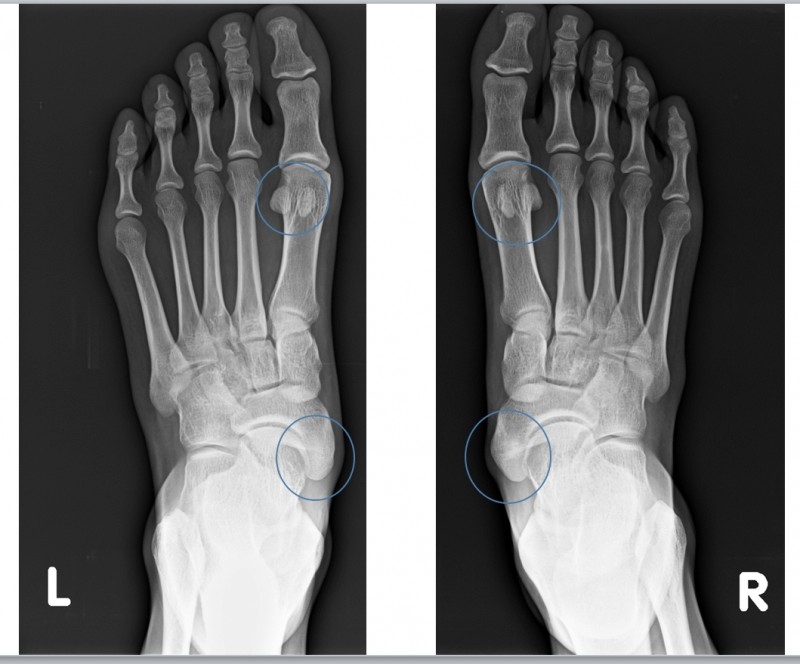

주요 증상: 엄지발가락이 둘째 발가락 쪽으로 기울고 첫 번째 중족골 머리가 돌출됨

호발 연령: 주로 중년 여성, 가족력이 있는 경우 더 흔함

통증 패턴: 튀어나온 관절 부위 통증, 신발과 마찰로 인한 굳은살, 염증

유발 요인: 유전적 소인, 좁은 신발 착용, 관절염, 편평족

진단 방법: 육안으로도 확인 가능, X-ray로 변형 정도 측정

부산무지외반증 은 엄지발가락이 바깥쪽으로 휘어지면서 발 안쪽에 돌출부가 생기는 질환으로, 심한 경우 관절염으로 진행될 수 있으며 특히 여성에게 많이 발생합니다.

유전적 요인도 있지만, 좁고 앞이 뾰족한 신발을 오랫동안 신거나 발에 맞지 않는 신발 착용이 주요 원인입니다.

아침에 통증이 심해지는 이유는 수면 중 발의 자세가 변화하면서 변형된 관절에 압력이 가해지기 때문입니다.

또한 밤새 약간의 부종이 생긴 상태에서 아침에 갑자기 체중을 실으면 변형된 관절 부위에 통증이 더욱 심해집니다.

주요 증상: 발의 내측 아치 부분(주상골 근처)에 여분의 작은 뼈가 존재

호발 연령: 주로 청소년기에 증상이 나타남, 여성에게 더 흔함

통증 패턴: 발의 내측 중앙 부위 통증, 특히 활동 후 심화

유발 요인: 외상, 과사용, 꽉 끼는 신발, 평발과 연관된 경우가 많음

진단 방법: X-ray나 CT로 추가적인 뼈 확인, 발의 내측 돌출과 압통

부산부주상골증후군 은 발의 안쪽 아치 부분에 위치하는 작은 추가 뼈로, 사람에 따라 뼈가 있기도 하고 없기도 합니다.

이 뼈가 있는 경우 주변 인대나 건에 염증을 일으켜 증후군이 발생할 수 있습니다.

아침에 통증이 심한 이유는 밤새 휴식 상태였던 발이 갑자기 체중을 받으면서 부주상골 주변 조직에 압력이 가해지기 때문입니다.

특히 발의 안쪽 아치 부분에서 통증을 느끼게 됩니다.